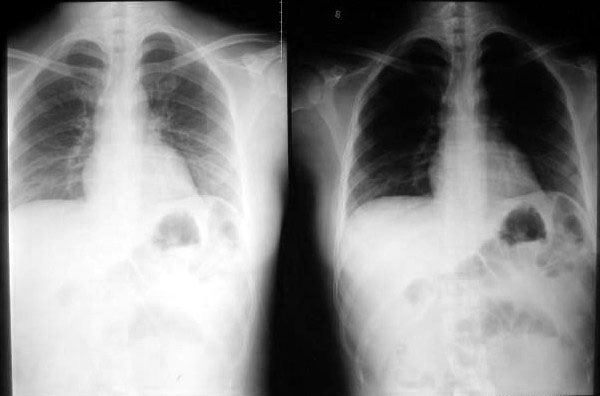

第二张03年

考虑隔疝

按楼主给出的片子时间,顺序说明病变有可恢复性及复发性,也只有左膈疝了,并且是可复性疝。

左侧隔疝.

典型左侧可复性隔疝

本例的诊断各位已经很肯定了---左侧膈疝。

膈肌有七个薄弱点:主动脉裂孔、下腔静脉裂孔、食道裂孔,及双侧对称的腰肋三角、胸肋三角。

膈疝常见于食道裂孔、胸肋三角、腰肋三角。

如果膈肌发育异常或后天外伤后破裂,可直接形成膈疝。

本例疝出的胃结构较大、较多,考虑为膈肌发育异常可能性大。经生理裂孔可能性小。

食道吞钡做得不完善,应该使胃部显影并加照卧位,找出疝环。

有没有可复性很难说,以前可复并不等于现在也可复,所以还是不要轻易下可复性疝。